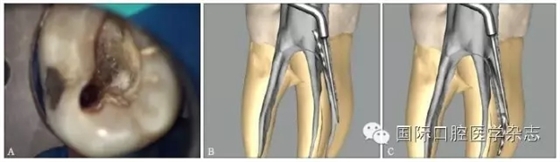

根管預(yù)備是根管治療最重要的步驟之一,預(yù)備根管后可以有效沖洗根管,清除根管內(nèi)微生物,為根管充填提供空間。由于種種原因,例如擴(kuò)孔鉆、根管銼、拔髓針等根管器械在操作時(shí),如果超過(guò)器械的極限強(qiáng)度,或者材料強(qiáng)度不能耐受正常的臨床加載力時(shí),器械就可能會(huì)分離在根管中(圖1)。

圖 1 根管內(nèi)分離的各種器械